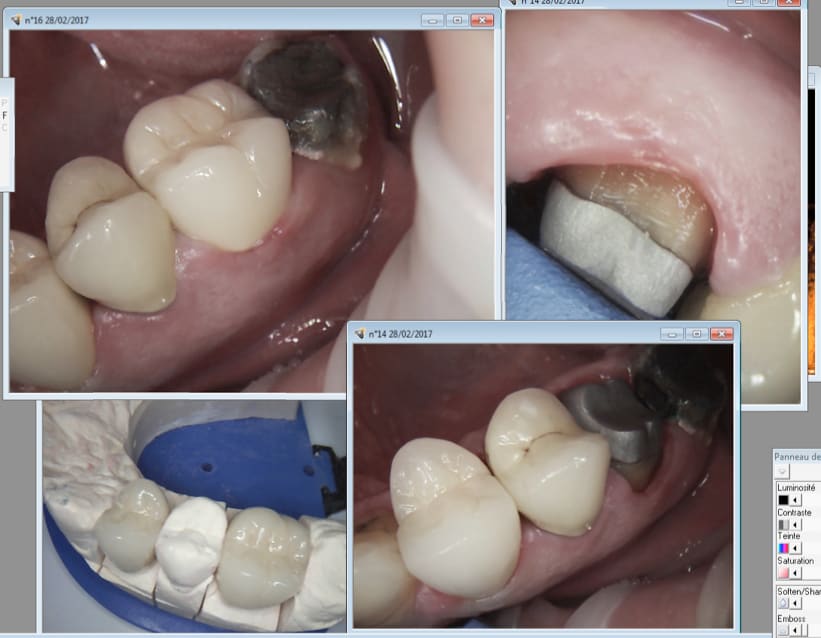

Pts de contacts OK, occlusion ok, adaptation inlay core oK. C'est l'essentiel.

Anatomie moyenne, mais comme le font aussi bien certains labos francais.

Tu t'en branles de la teinte en postérieur. C'est peut etre moi qui ne suis gourré. -)))

Mise en place nickel pas de retouches basta. 60 euros de moins que le protho habituel. mais là n'est pas l'important. Un peu plus et je pourrais faire mon endio molaire gratuite sans que ca change quoique ce soit pour moi. C'est ca qui est lamentable.